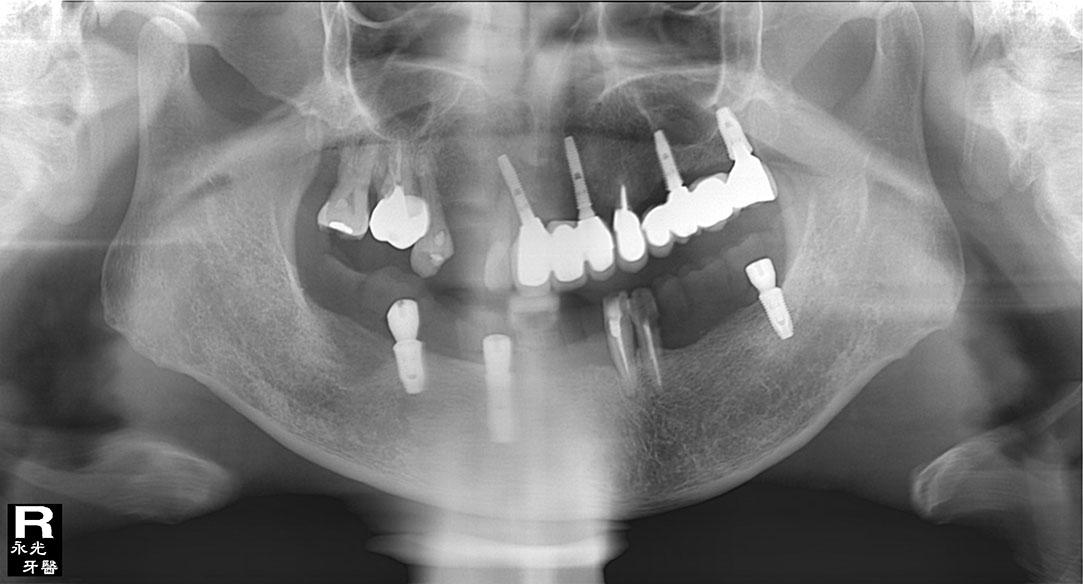

Implant 80d2.jpg

光牙醫